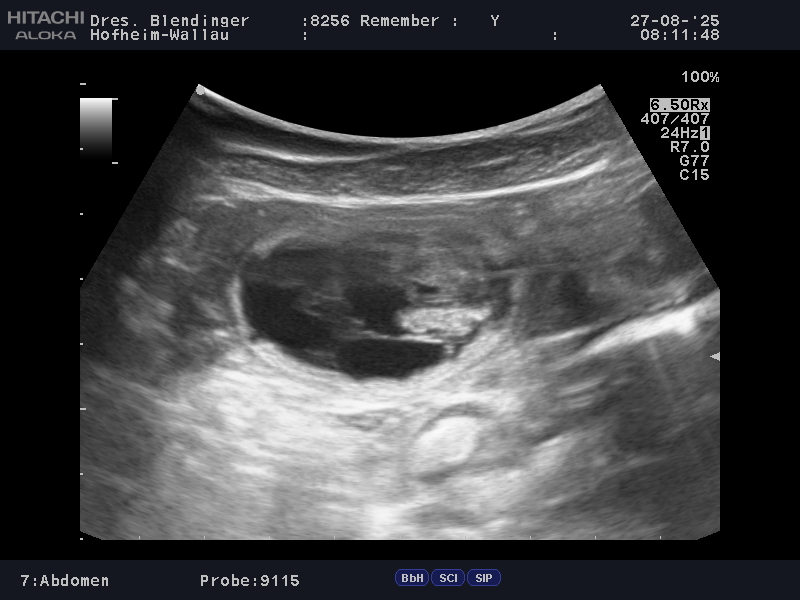

Nach dem positiven Ultraschallbefund heute ist es amtlich… Unser Mädel ist trächtig !!! Remember hat damit gezeigt, dass sie sich doch in die erfolgreichen fruchtbaren Ahnen (mütterlich) einreihen kann. Die Tierärztin konnte 6-8 Fruchtblasen erkennen.

Die Geburt erwarten wir mit Spannung Ende September.